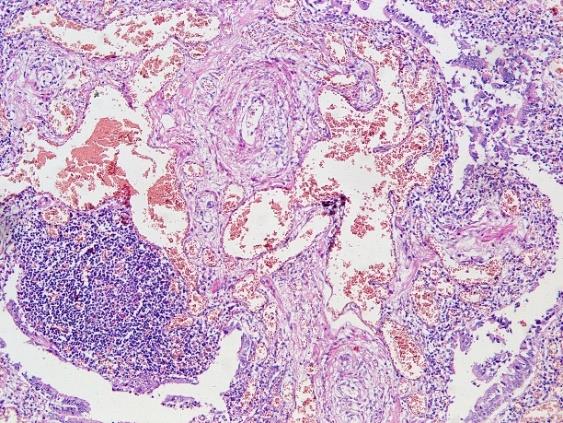

2)心脏肥大,重380g,心尖钝圆,右心室壁增厚,右心室扩张;胸膜肥厚、粘连,肺细小动脉肌化,中膜增生、肥厚,急性肺淤血,肺部慢性炎症,灶状肺气肿;冠状动脉左前降支及左旋支病变Ⅱ级。

3)双侧部分胸膜呈纤维素性渗出伴机化增厚改变;双肺支气管周围见以淋巴细胞为主、伴浆细胞浸润,管腔内可见少量黏液栓形成;双肺肺泡间隔部分纤维性增厚,毛细血管充血、扩张,肺泡腔可见大量水肿液、巨噬细胞增生并周围肺泡过度充气及肺气肿改变,同时可见局部无肌性细动脉肌化及肌型小动脉中膜增厚、肺组织少量纤维性结节增生、多发性微脓肿形成。

右肺下叶,HE,×100 左肺上叶,HE,×100

肺细小动脉肌化、中膜增厚,急性肺淤血,慢性炎性细胞浸润